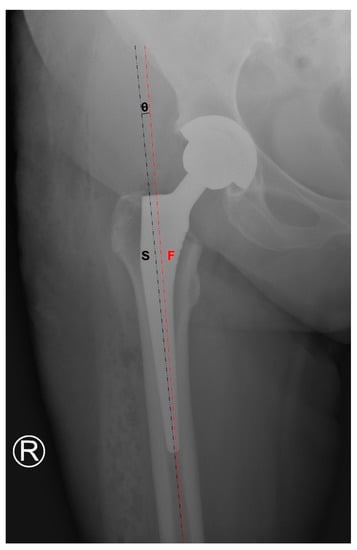

3.2. Femoral Stem Alignment

3.3. Mean Radiographic Cup Inclination